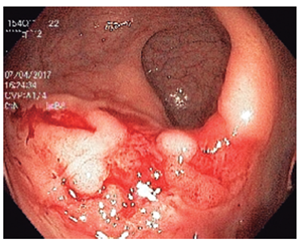

Varios estudios han demostrado la utilidad de los procedimientos endoscópicos en este contexto. Se debe aclarar que no hay un patrón endoscópico típico de infección por oportunistas, por tanto, siempre se deben tomar biopsias. Se sugiere que la infección por Salmonella predomina en el colon derecho y va desde un eritema hasta ulceraciones. La infección por amebas suele afectar el ciego y rectosigmoide, con ulceraciones y zonas de necrosis (Figura 4 ). El CMV puede generar ulceraciones que predominan en el colon izquierdo (Figura 5 ). El rendimiento de la colonoscopia va desde el 27% al 39%, y el CMV es el germen más común 38.